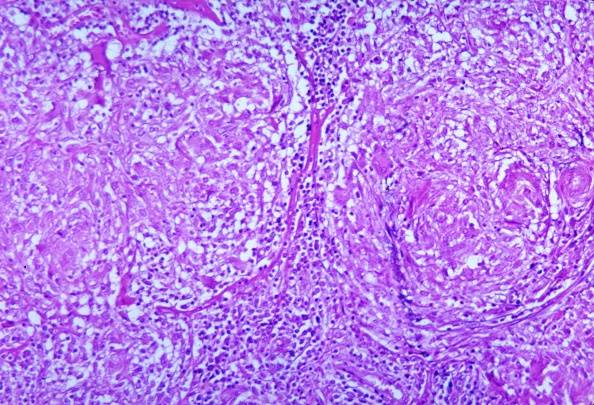

The advisory issued on Dec. 25, 2025 is to alert clinicians and laboratories to an increase in pulmonary and disseminated histoplasmosis cases in Middle Tennessee.